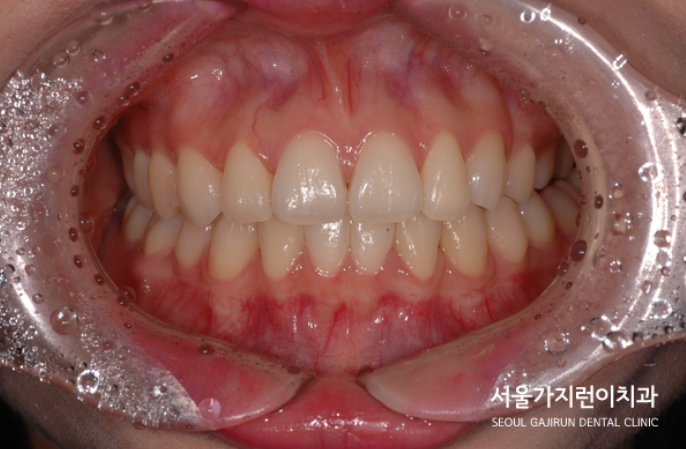

이미 발치가 된 하악과 곧 발치가 필요한 어금니, 게다가 덧니와 더불어 흐트러진 치열까지 밸런스를 맞추기 쉽지 않은 케이스였는데요. 무엇보다 한쪽은 대구치, 한쪽은 소구치여서 발치 공간의 크기가 달라 중심선을 맞추고 정상 교합으로 맞추기가 쉽지 않은 경우였습니다. 하지만 저희는 교정전문치과잖아요. 사랑니를 세우는 교정과 더불어 덧니교정까지 진행해봤습니다.

발치된 공간은 임플란트를 식립하지 않고 공간을 폐쇄하는 쪽으로 진행했으며 하악의 경우에는 사랑니를 세워 새로운 어금니로 활용할 수 있도록 교정을 진행했는데요. 상하악 모두 발치 공간이 닫히는 모습을 과정 사진으로 확인할 수 있겠습니다.

무슨 교정을 이렇게까지 해야 하나... 싶지만 임플란트 기술이 아무리 좋아져도 자연치아를 따라갈 수는 없는데요. 시간이 오래 걸린다하더라도 자연치아 한 개의 가치를 얻을 수 있다면 해당 교정방식을 통해 씹는 힘을 회복해보는 게 더 현명한 선택일 수 있겠습니다.